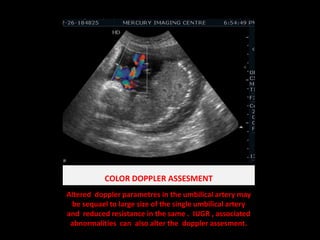

COLOR DOPPLER ASSESMENTAltered  dopplerparametres in the umbilical artery may be sequael to large size of the single umbilical artery  and  reduced resistance in the same .  IUGR , associated abnormalities  can  also alter the  dopplerassesment.